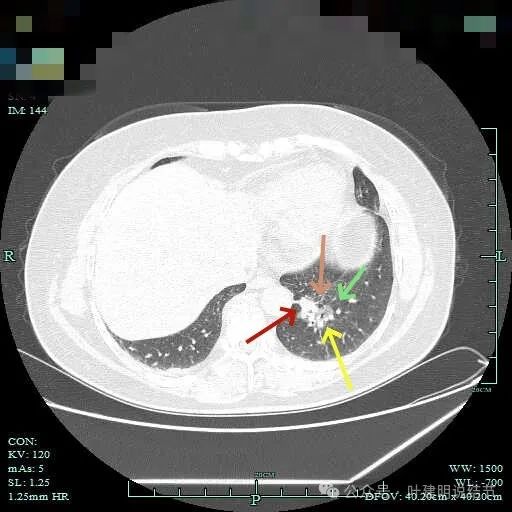

磨玻璃成分以及灶内空泡征。

灶内细支气管扩张明显,实性成分缺乏收缩力,考虑腺泡亚型。

磨玻璃成分也很明显,考虑含贴壁亚型。

上图大部分是磨玻璃成分,边缘的毛刺征,表面有浅分叶。

上图层面已经基本上磨玻璃密度,轮廓清,灶内有囊腔样灶,表面不平。